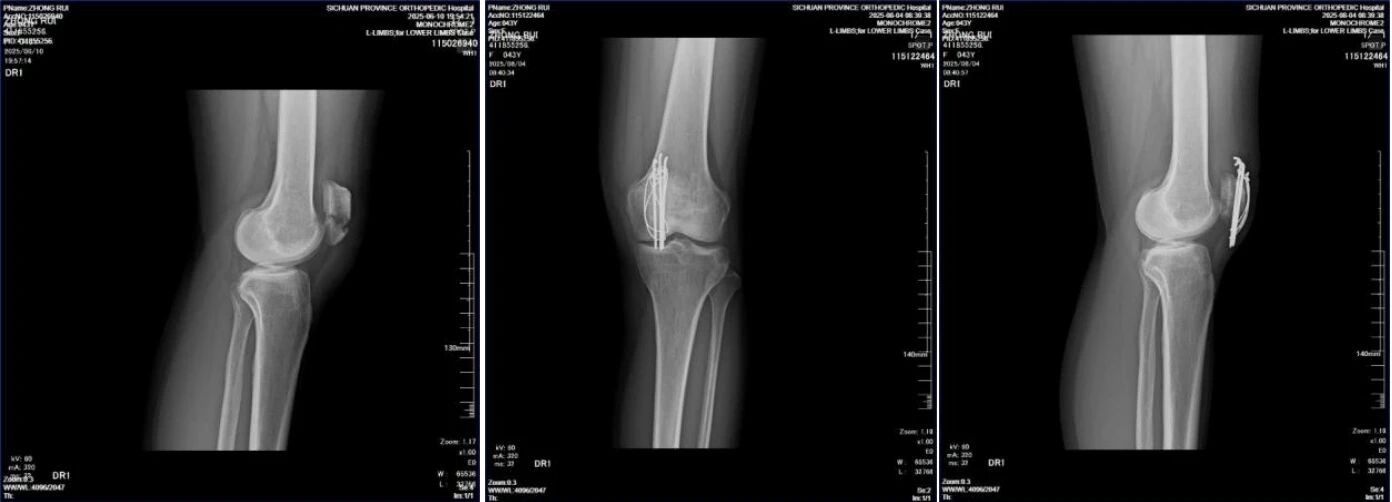

43岁女性患者,左髌骨骨折。

自左向右:术前DR侧位片,术后1月复查DR正、侧位片